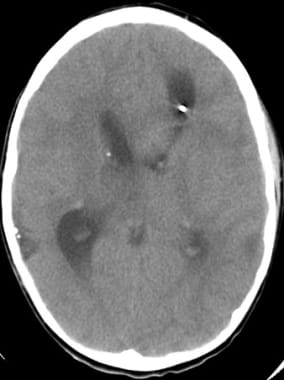

Hydrocephalus from a subependymal giant cell astrocytoma in a patient with tuberous sclerosis. The patient presented with acute blindness and ataxia.

Subependymal giant cell astrocytoma prior to stereotactic insertion of balloon catheter as seen on T2-weighted MRI.